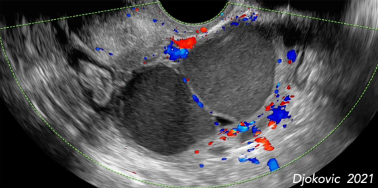

- TVUS: Uterus retro? Zeichen einer Adenomyosis (ungleiche Dicke von Hinter- u. Vorderwand, inhomogene Bereiche, Lakunen, hyperechogene Spots, inhomogene Perfusion, Endo-Myometrane Junktionszone, Question-mark Sign, Rain in the Forrest Phänomen)? Uterus auf eine Seite verschoben? Ev. Septum recto-vaginale mitbeurteilen. Douglas frei? Harnblasenwand, Hinweis auf RF? Ovarien: Endometriome?, ev. AFC je nach Fragestellung Kinderwunsch, Mobilität des Situs beurteilen.

- Diagnose i.d.R. durch TVUS

- typ. sonomorphologischer Aspekt: runde oder entrundete, z.T. gewunden/ gekammert imponierende Zysten mit homogenem Inhalt, mässige Echodichte (sämiger Aspekt)